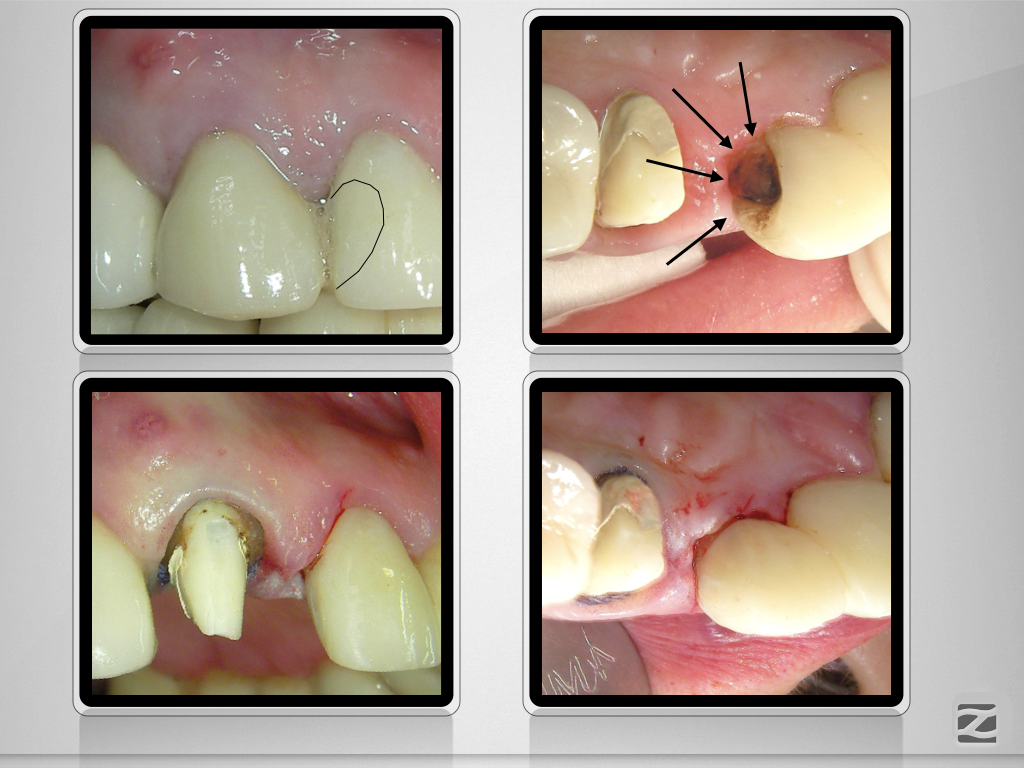

13D.007 Veröffentlicht 21. Januar 2020 am 1024 × 768 in Wer hat Angst vor’m bösen Stift? Teil 2, Zirkonoxidstift